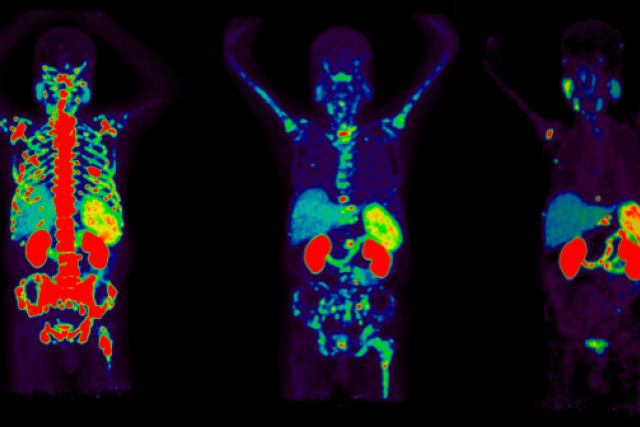

Certain radioisotopes emit radiation which is not harmful to cells and can be imaged using positron emission tomography (PET). This is the diagnostic part of theranostics. Others emit radiation which can damage and even kill cells. This is the therapeutic part.

In theranostics, doctors administer a specialized molecule called a radiotracer that can hold a radioisotope and target cancer cells. The radiotracer then binds to the cancer, allowing doctors to see exactly where it is and deliver cell-damaging radiation directly to it. This “see what you treat” approach helps doctors diagnose, stage, and treat cancer while minimizing damage to healthy tissues.

- Diagnostic Phase: To see where the cancer is, an imaging radiotracer will be administered by your health care team in our outpatient clinic. You will then undergo a full-body PET scan which will create pictures showing where the radiotracer goes. The whole process typically takes less than 3 hours, after which you can leave the clinic.

- Therapy Phase: To treat the cancer identified in the Diagnostic Phase, your health care team will administer a therapeutic radiotracer in our outpatient clinic. Following administration, you will be closely monitored by your care team for two to three hours, after which you will be able to leave the clinic. The number of therapy cycles you undergo will depend on the disease being treated, but can range from one to six.

After completing all treatment cycles, your health care team may perform another PET scan to monitor how the cancer has responded to the treatment.